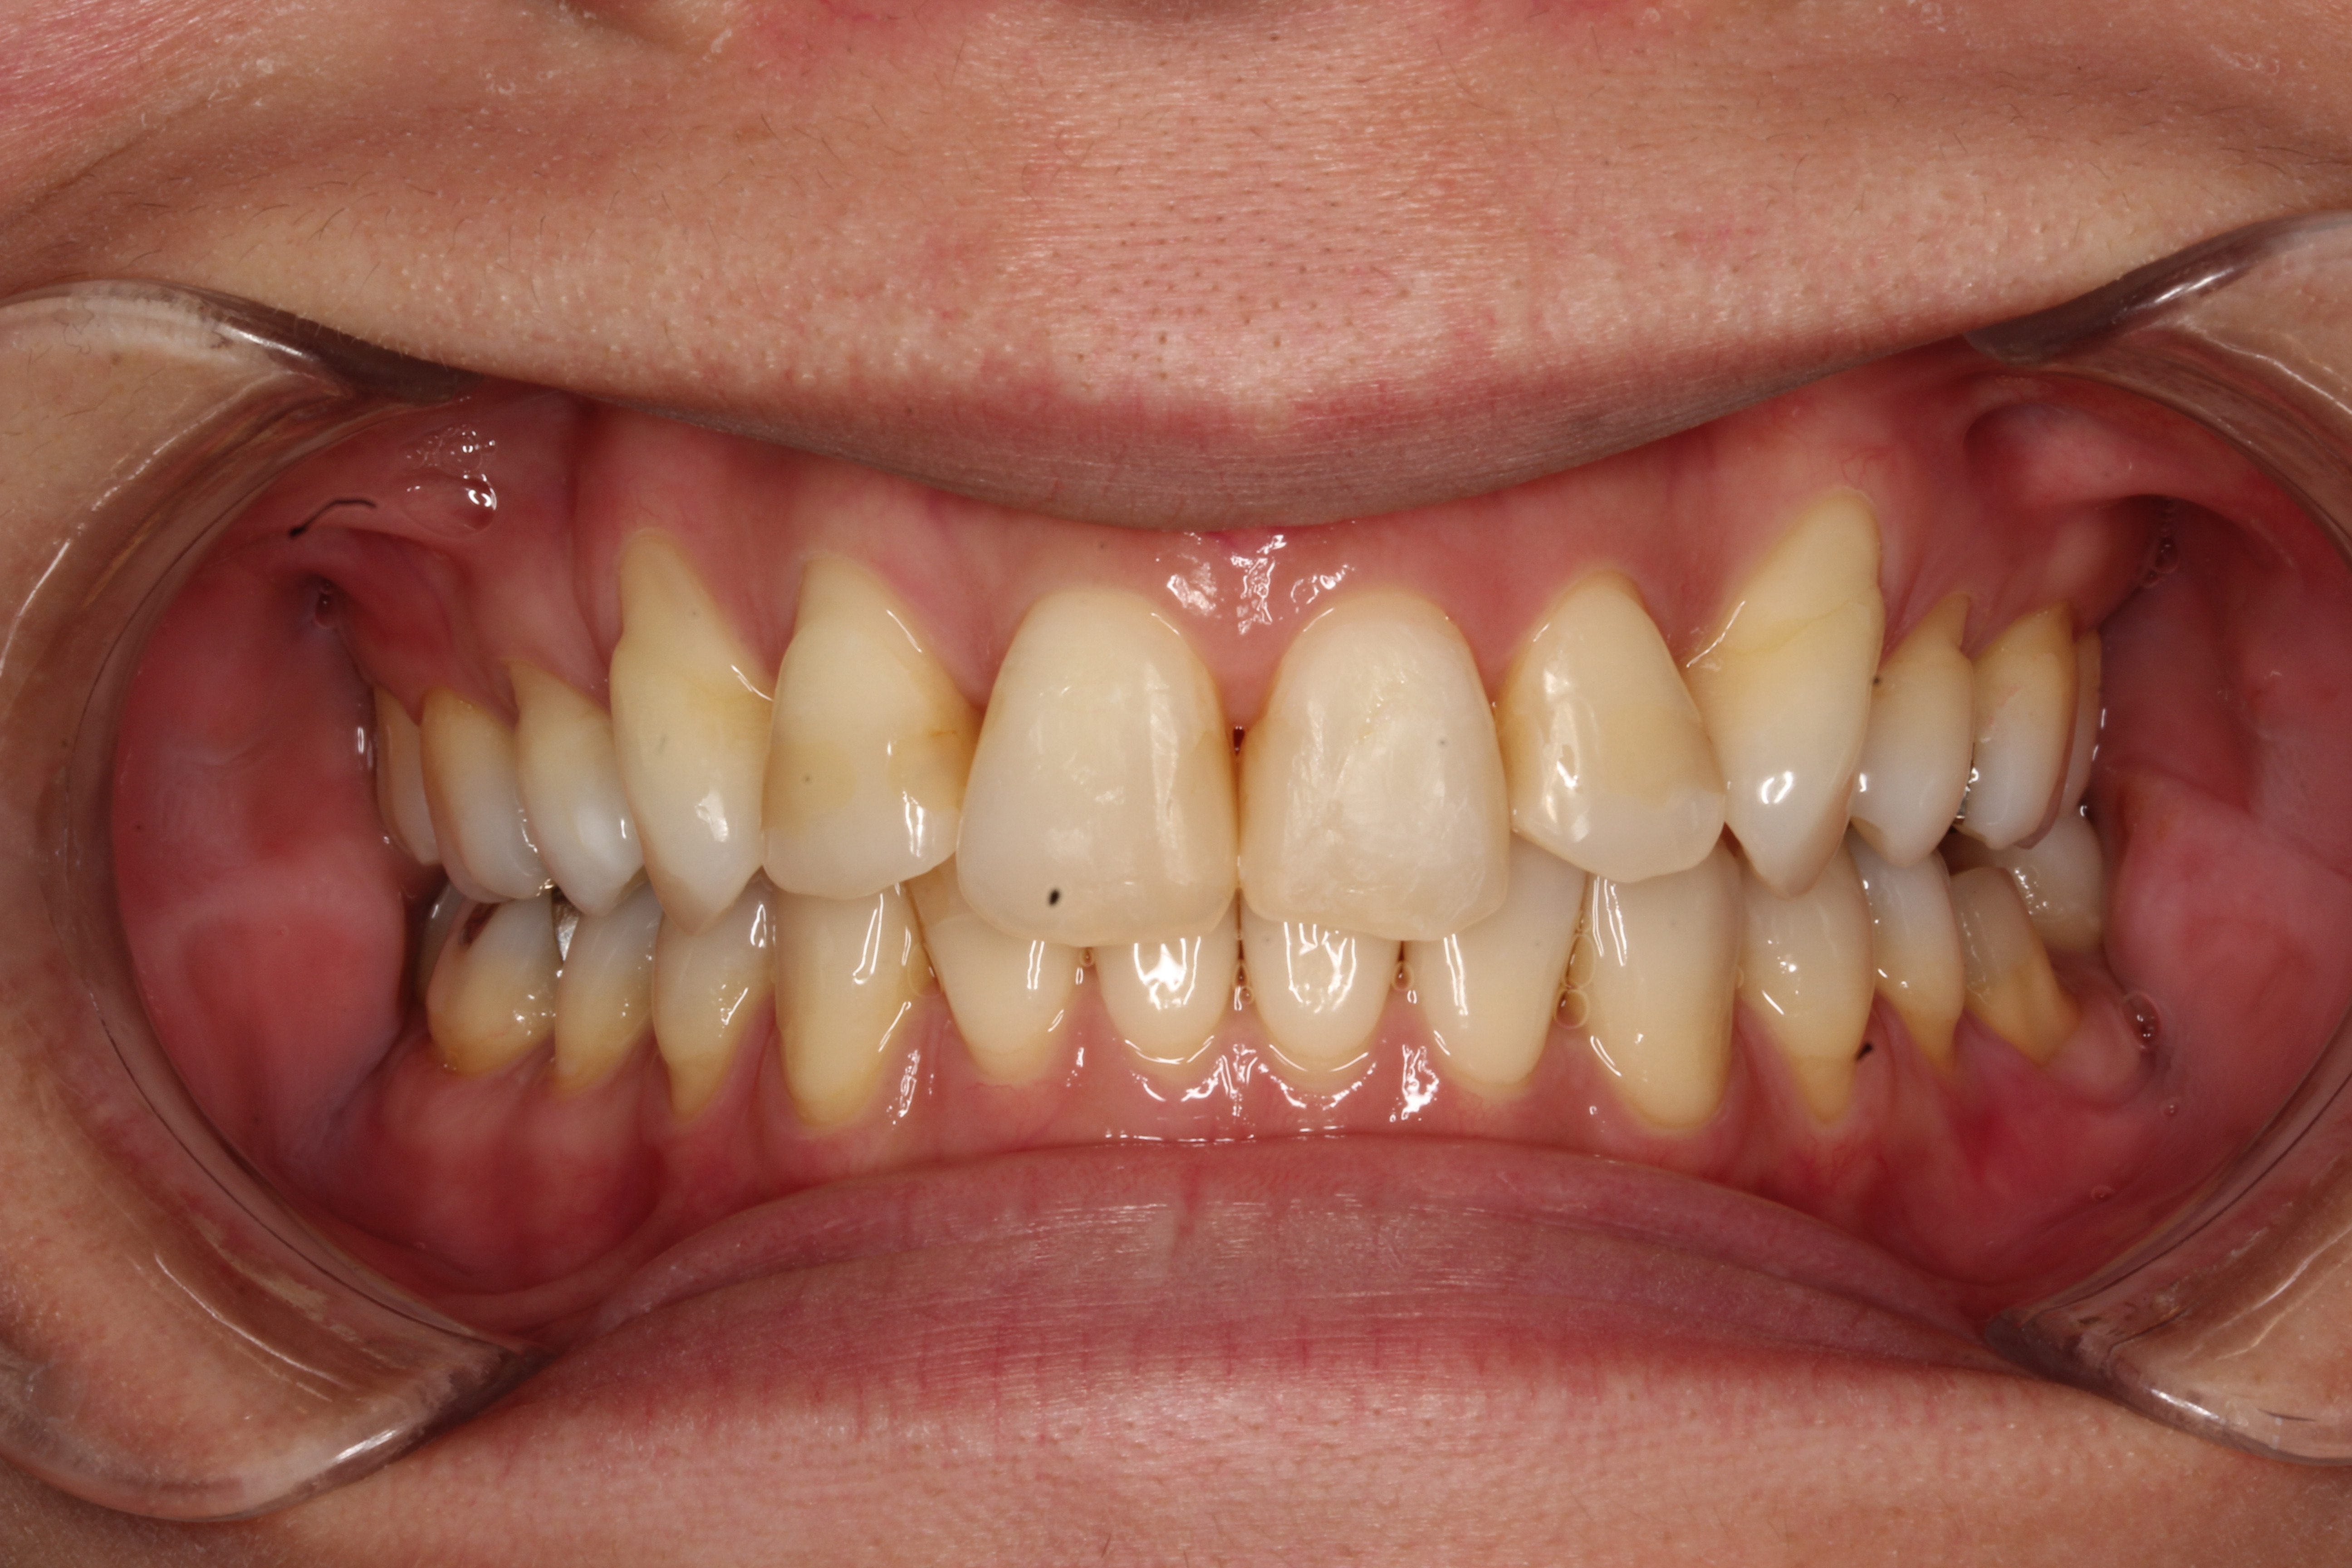

初診

Before

終了時

After

八重歯を改善したい

主訴 【主訴】凸凹を治したい 【診断・症状】叢生・上下顎劣成長・交叉咬合・下顎右方偏位

治療費用 検査・診断:38,500-/表側矯正治療:1,155,000-(※全て税込)

治療期間 約2年10か月(34回)

抜歯 抜歯:有(上4,4・下5,5)

矯正の装置 表側矯正

副作用、リスク 歯肉退縮・歯根吸収・疼痛・咬合の違和感・装置の違和感・正中のズレ